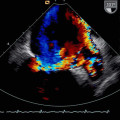

El diagnóstico de las enfermedades cardiovasculares se basa en una historia clínica detallada que incluye el estudio de los antecedentes familiares y personales de riesgo y una completa exploración física. Se utilizan diversas pruebas diagnósticas complementarias, como son fundamentalmente el electrocardiograma, el ecocardiograma -doppler color, los registros ambulatorios de presión arterial y actividad eléctrica del corazón y la prueba de esfuerzo o test ergométrico que se realizan todas en nuestra consulta y ninguna de ellas, requiere una preparación previa especial del paciente. Pruebas adicionales de diagnóstico como test farmacológicos y genéticos, tilt-test o prueba de la mesa basculante para estudio del síncope, técnicas avanzadas de imagen como la Ecocardiografía transesofágica, Ecocardiografía 3D, Resonancia Cardiaca y el Angiotac coronario ó pruebas invasivas como los estudios electrofisiológicos y el cateterismo cardiaco, se realizan en nuestros Hospitales Madrid Montepríncipe y Madrid Torrelodones, por expertos con el mayor nivel de excelencia en la especialidad.

Ecocardiograma M y 2D, doppler pulsado/continuo y color.